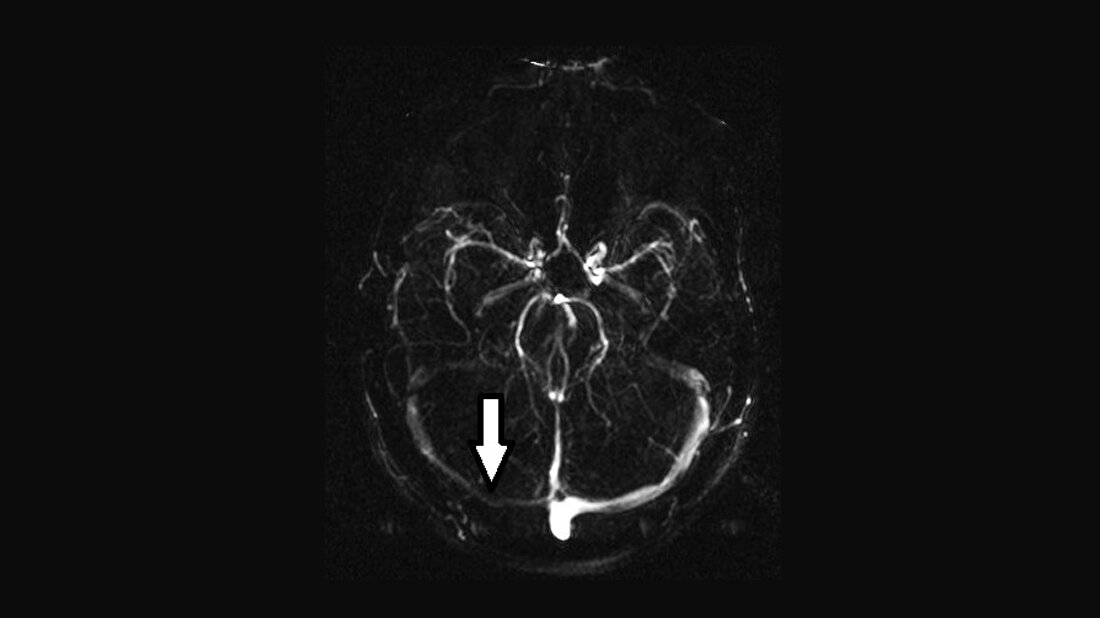

Anomalien und Normvarianten – kranielle Veränderungen 1.13: Asymmetrie des Sinus transversus

Die Hypoplasie des Sinus transversus kann prädisponierend zur Sinusvenenthrombose sein, stellt aber primär keine funktionelle Störung dar. Die Sinusthrombose kann durch die MRT von der Hypoplasie besser differenziert werden als in der Angiografie.

Schlüsselwörter: Hypoplasie Sinus transversus, Thrombose, CT, MRT